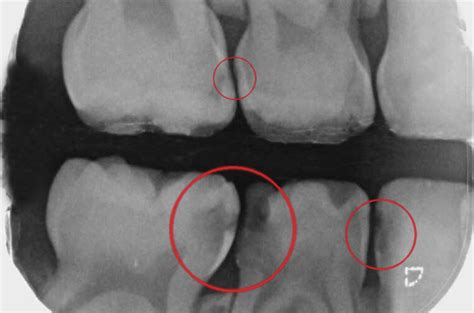

Diagnóstico de las Caries Interproximales

Como ya hemos mencionado anteriormente, las caries interproximales suelen ser complicadas de detectar a simple vista y por eso es necesario acudir al odontólogo para que nos las diagnostique a tiempo. Son muy importantes las revisiones periódicas en el dentista para poder detectar las caries interproximales de forma precoz. Será el especialista quien, mediante una radiografía, pueda hacer un diagnóstico y aplicar el tratamiento para las caries interproximales más adecuado.

Para poder asegurarnos de que el paciente sufre de caries interproximales, el odontólogo le realizará una radiografía oral y una exploración dental. De está manera, podrá detectar las caries interdentales a tiempo y tratarlas.

La prueba diagnóstica más adecuada para las caries interproximales será una radiografía oral y una exhaustiva exploración dental.